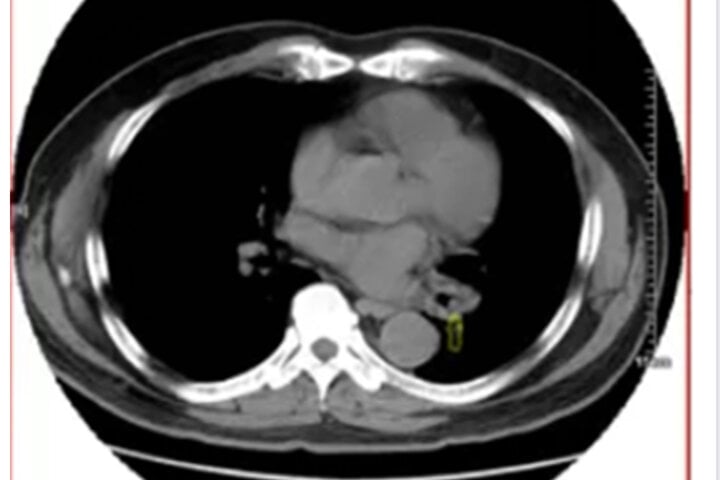

Ảnh chụp phổi của ông Long. (Ảnh: Sohu)

Ông Long tới bệnh viện Nhân dân Nam Ninh để khám bệnh. Bác sĩ nội soi phế quản cho ông và phát hiện khối u ở khe hở đáy phổi bên trái. Nó chặn lỗ mở của đoạn đáy phổi khiến ống nội soi không đi tiếp được. Hơn nữa, ông Long ho dữ dội nên họ đành dừng nội soi.